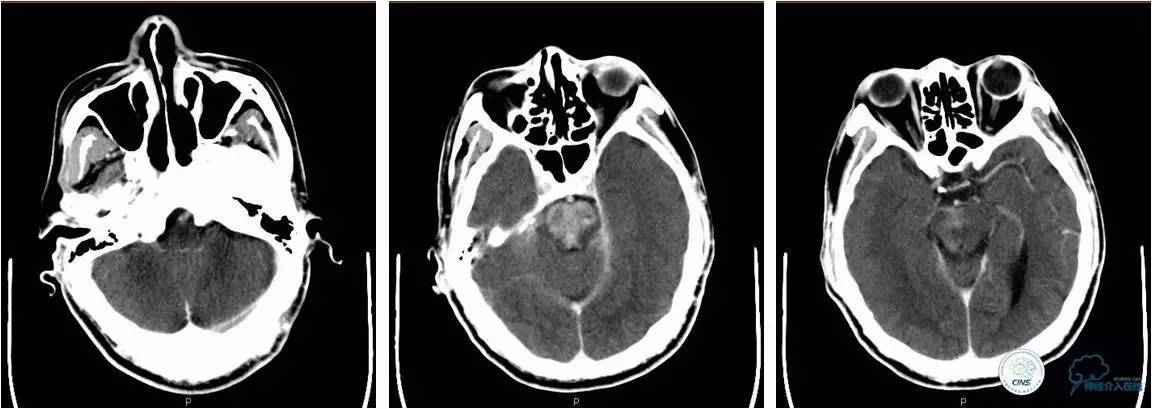

》术后复查头颅CT

★术后即刻头颅CT、术后6小时复查头颅CT,脑干内高密度影明显变淡,提示高密度影为造影剂外渗,不是出血。

即刻

6h后